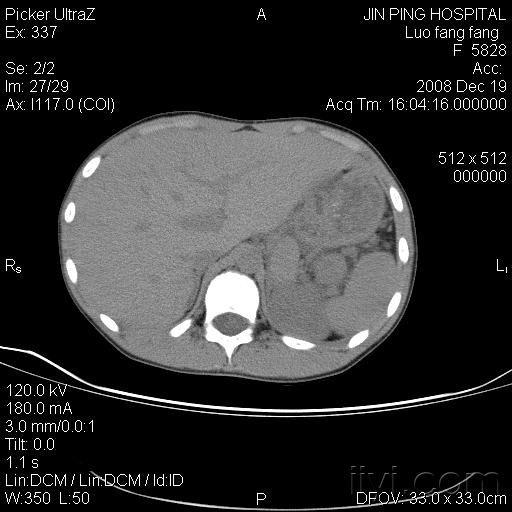

脾脏和副脾图片,副脾

已手术切除胰尾部及脾脏),证实为胰尾部异位脾脏 副脾是位于正常脾脏

副脾ct图片

副脾影像图片

副脾CT